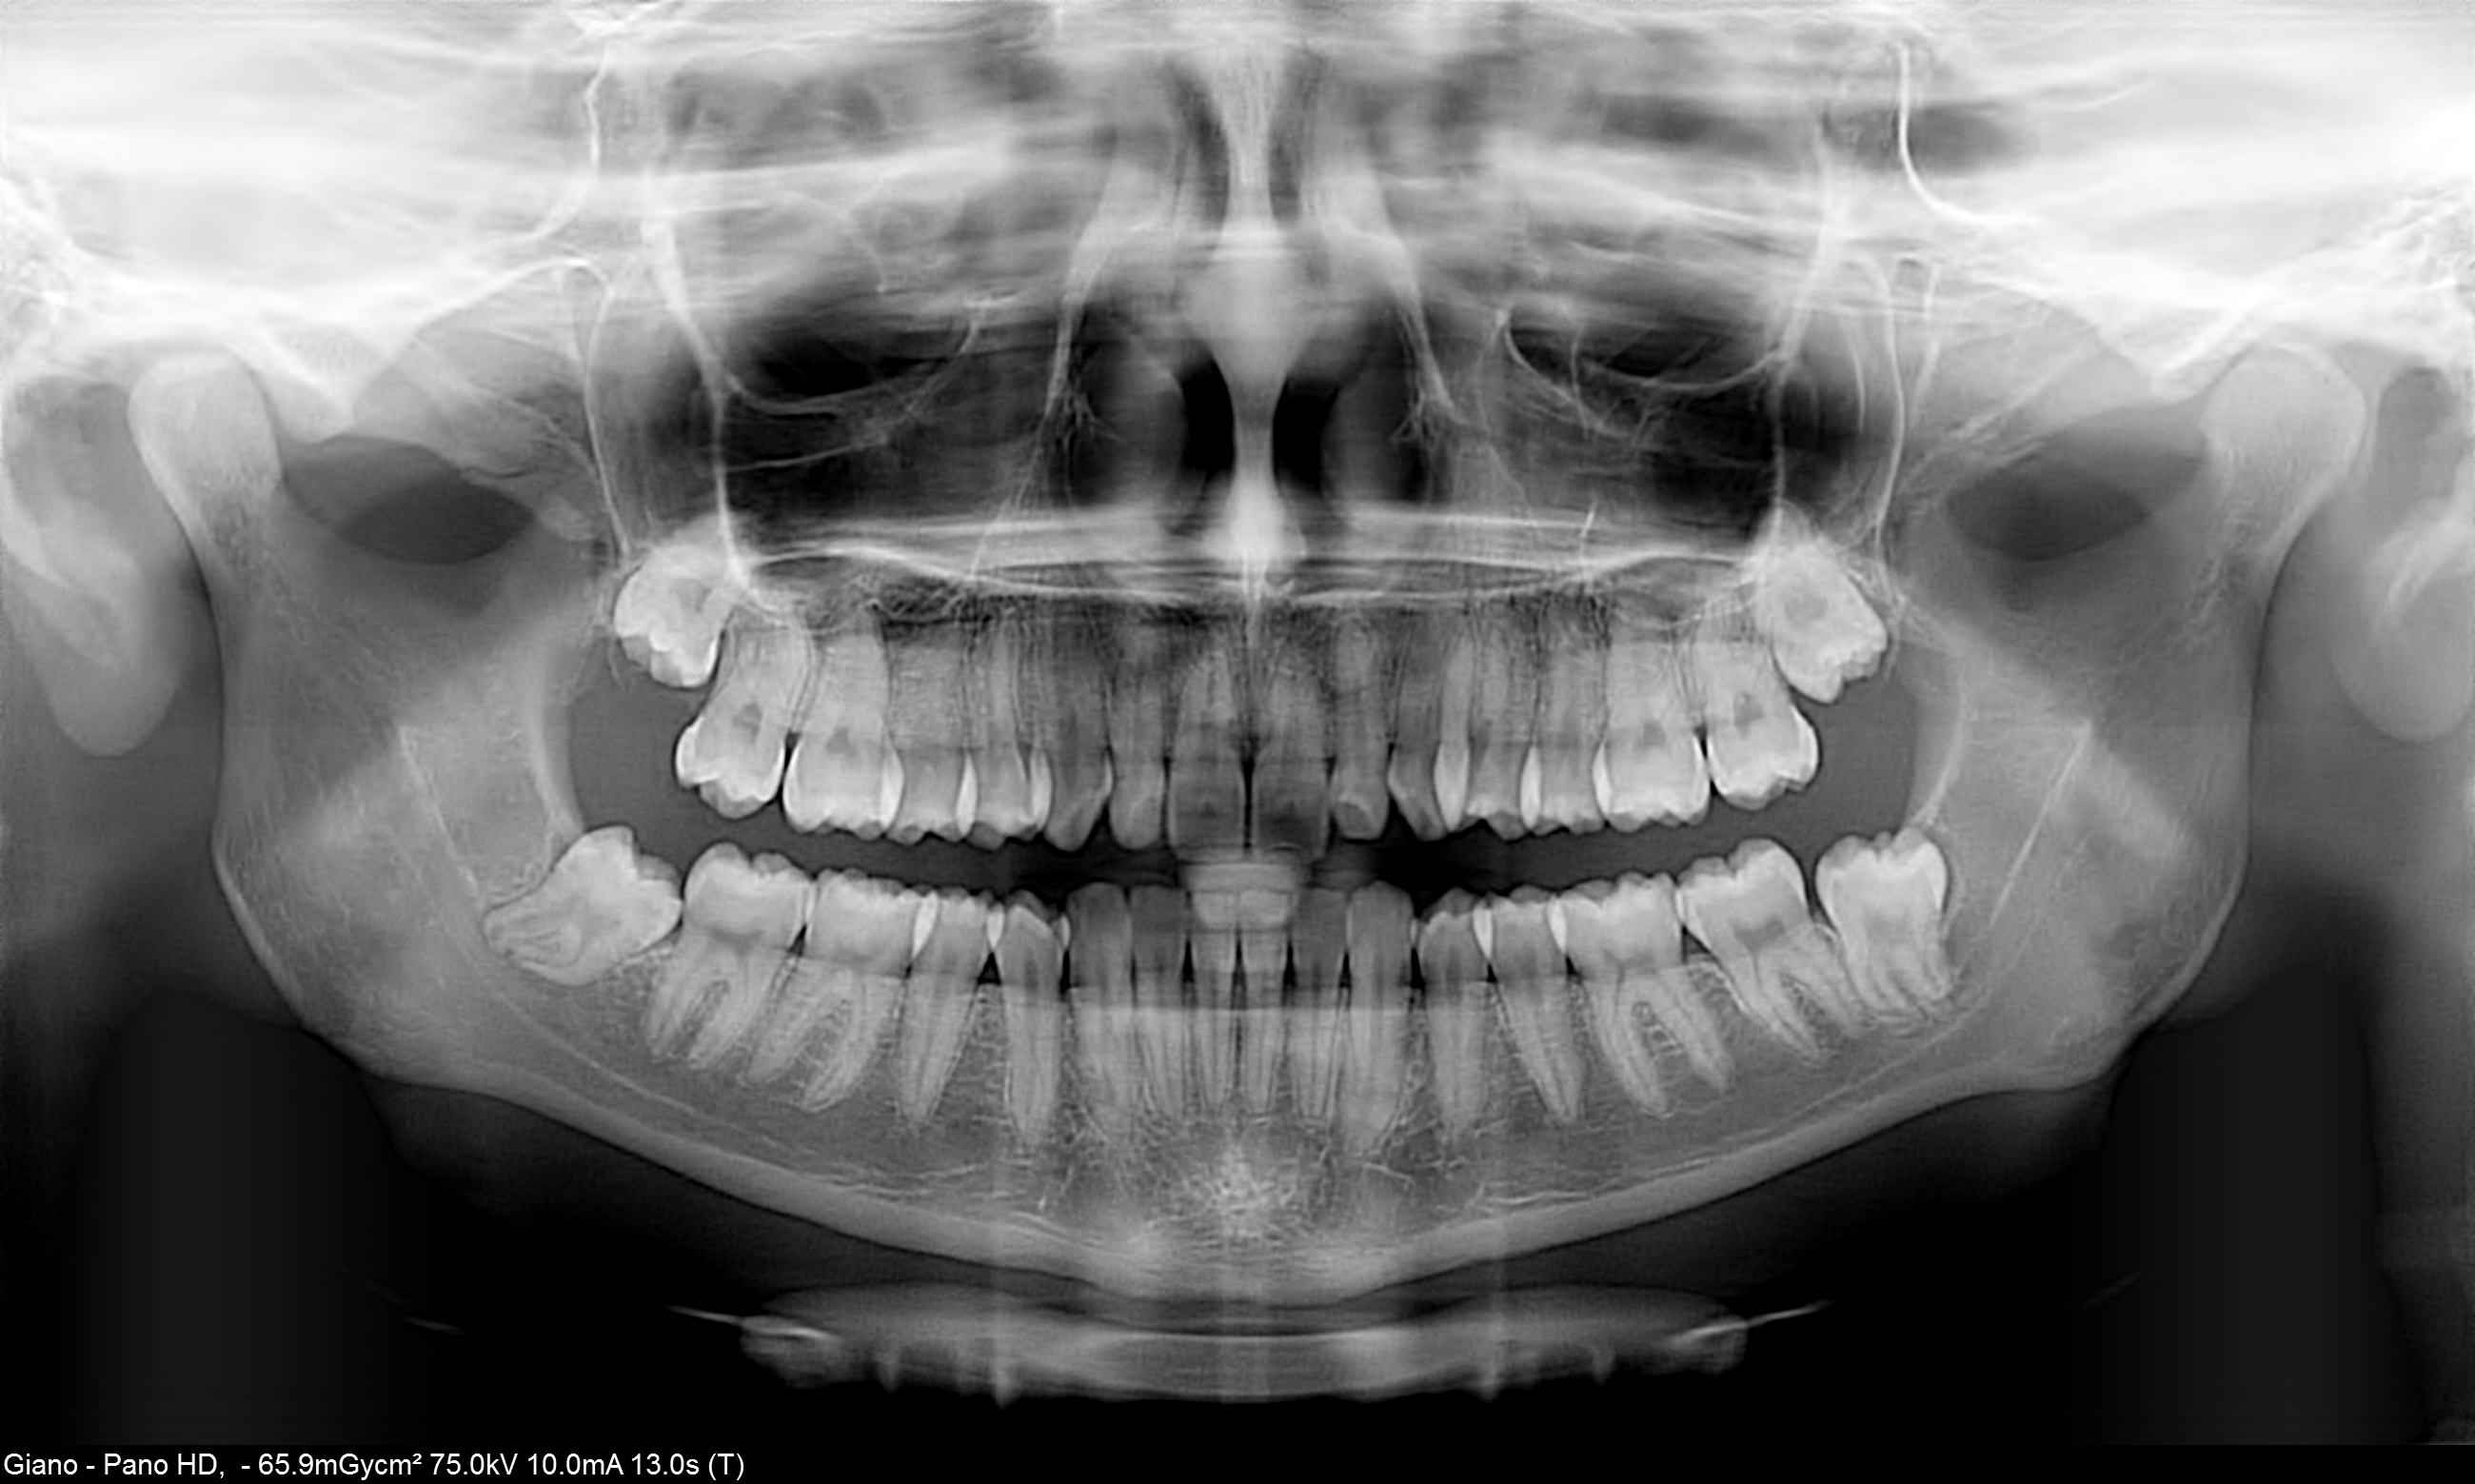

Una accurata valutazione del percorso del  nervo alveolare inferiore è indispensabile per la  corretta pianificazione di una avulsione del terzo molare inferiore e per garantire la massima sicurezza al paziente.

L'esame Ortopanoramico, benché minimalmente invasivo per il suo intrinseco basso dosaggio, a causa della sua natura bidimensionale potrebbe fornire informazioni inaffidabili riguardo la relazione tra il canale alveolare inferiore e le radici dei molari. Infatti in casi molto complessi questa informazione potrebbe essere insufficiente e quindi rendersi necessario un esame più approfondito.

Oggi l'Odontoiatra, grazie alla diffusione delle apparecchiature Cone-Beam 3D, ha la possibilità di effettuare valutazioni accurate, anche in studio, su questo tipo di casi con accuratezza ed affidabilità e con una bassa dose radiogena erogata al paziente.